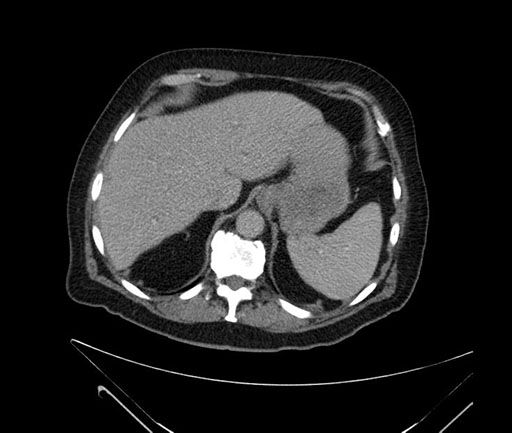

Imaging Analysis

Look through the patient's CT scan to identify any areas of concern for the necessary procedure.

Based on your CT findings, which issue(s) would give reason for "planned slowing down moment(s)" in this case?

Considering a standard Whipple procedure, what step(s) of the operation would you do differently in this case?